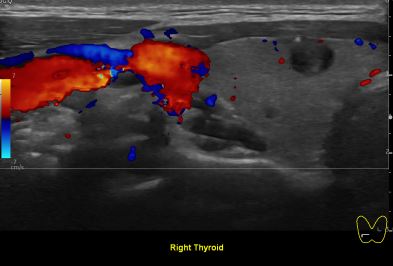

상기환자 외부건진 이상소견으로 내원하신 40대 초반 여성분으로

의심스러운 갑상선 우엽 세포검사후 갑상선암으로 진단되었습니다